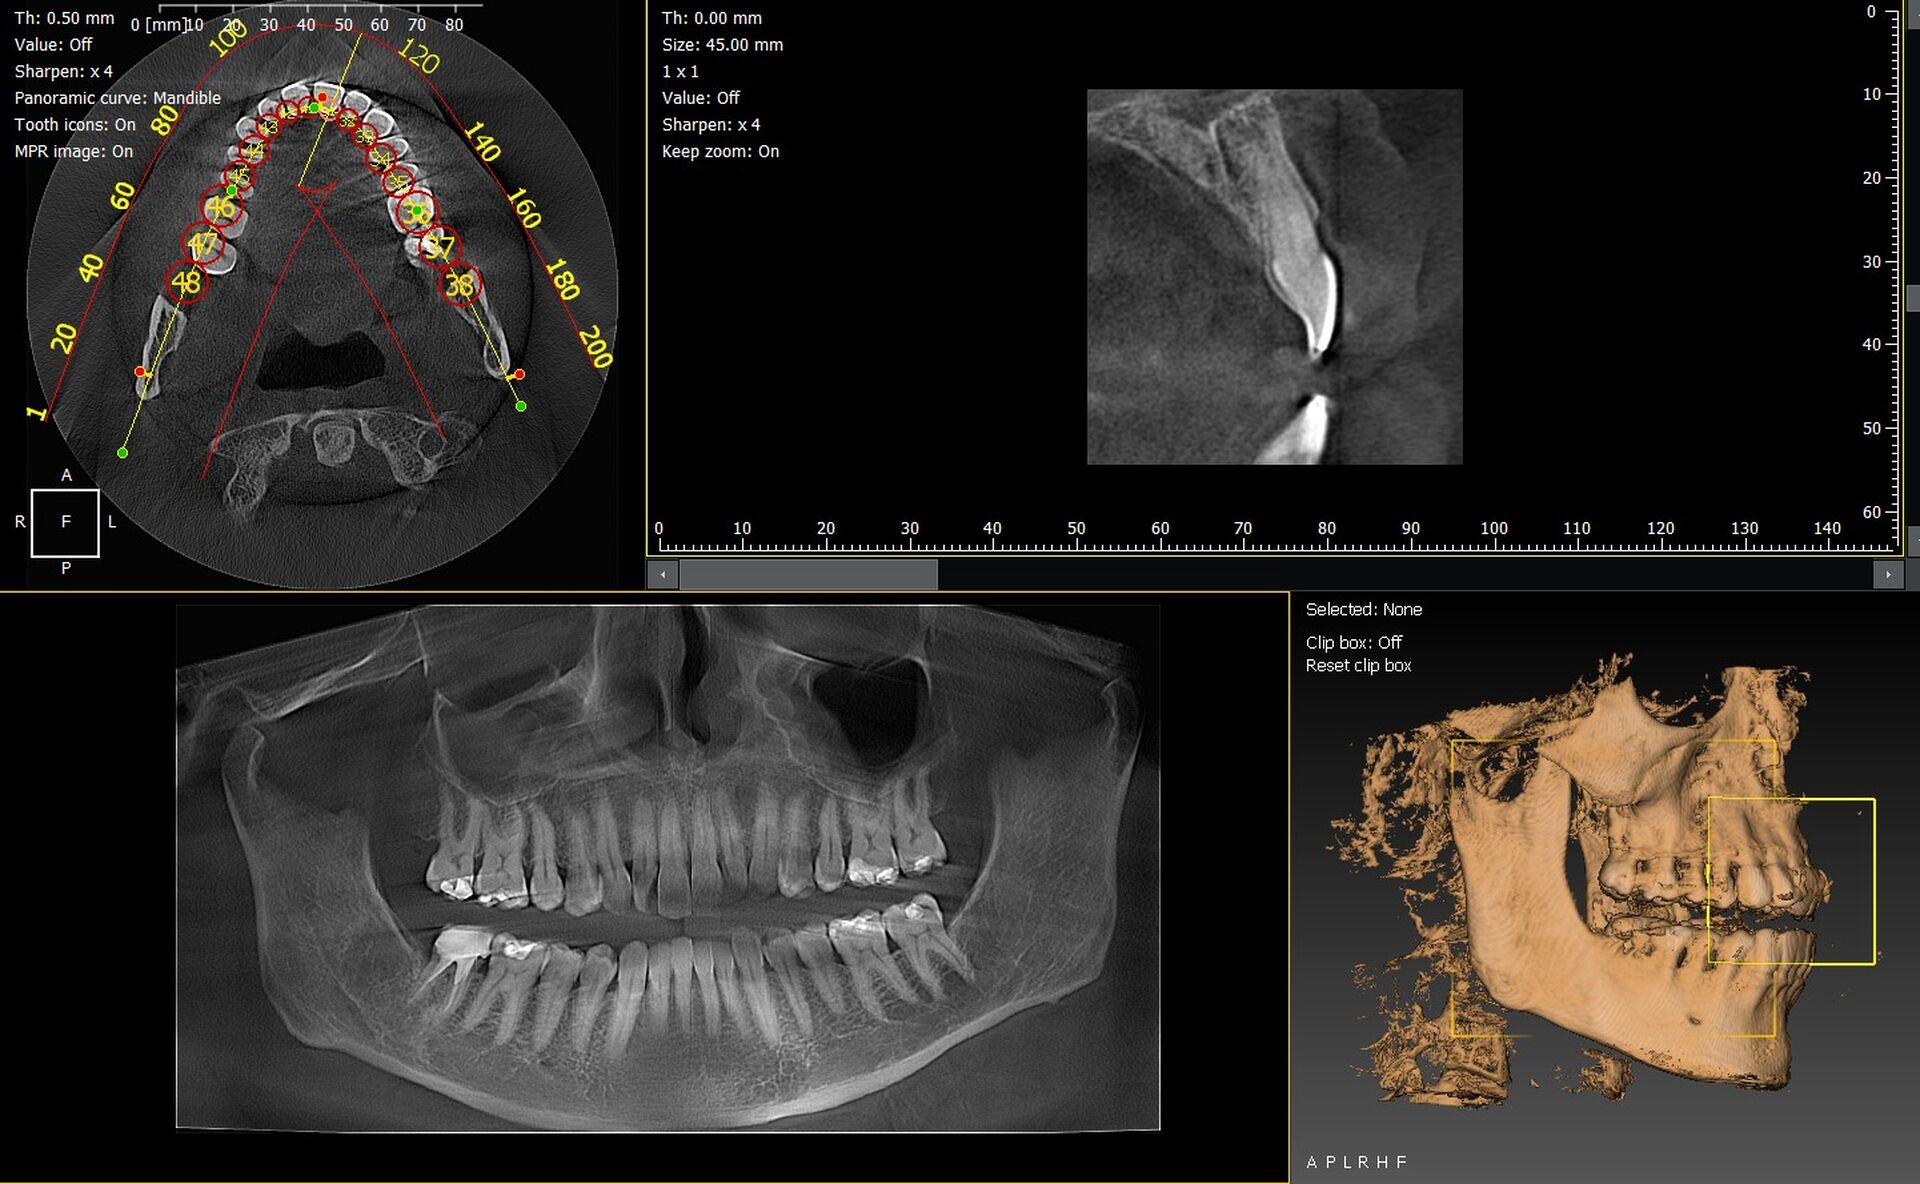

Les cabinets dentaires de Marseille et du département des Bouches du Rhône (13) modernisent leur plateau technique grâce à des solutions d’imagerie 3D fiables et hautement performantes. Les panoramiques CBCT 3D VistaVox de Dürr Dental et l’Owandy I-Max 3D comptent parmi les équipements les plus avancés, garantissant une qualité d’image exceptionnelle et un diagnostic d’une grande précision.

VistaVox 3D : précision maximale et volume optimisé

Le VistaVox se distingue par :

• un volume d’exploration parfaitement adapté à l’anatomie dentaire,

• une résolution élevée pour implantologie et endodontie,

• une dose optimisée,

• un positionnement patient simple et rapide.

Owandy I-Max 3D : compact, intuitif et polyvalent

L’Owandy I-Max 3D offre :

• un design mural compact, idéal pour les cabinets urbains,

• des protocoles d’imagerie 2D/3D rapides,

• une excellente qualité d’image,

• une interface simple et ergonomique.